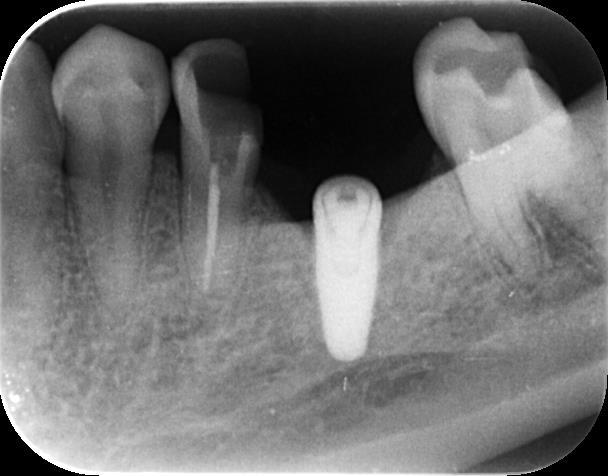

左下のデンタル写真